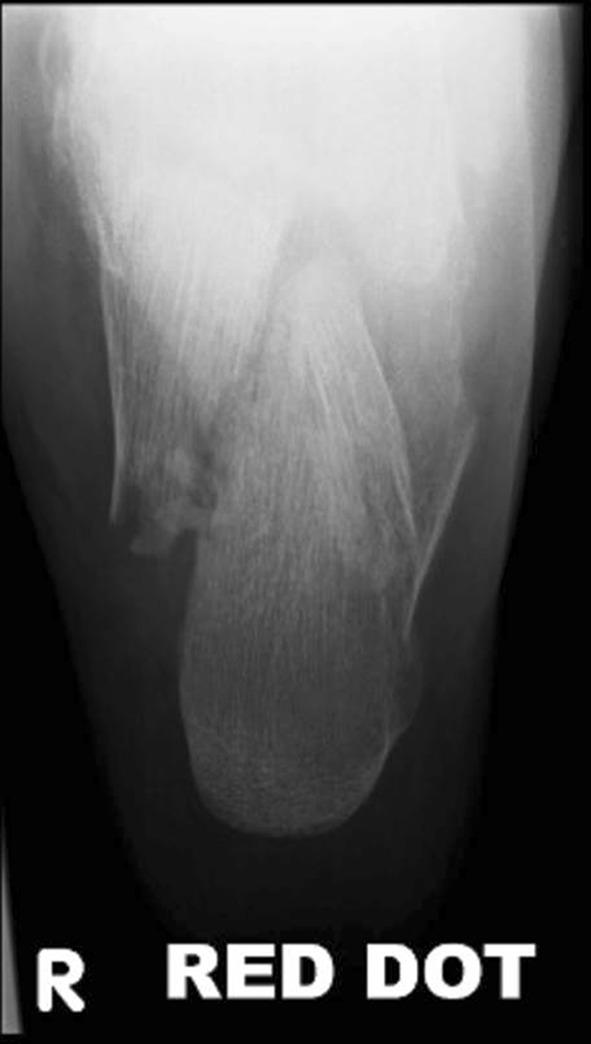

Calcaneal fractures: Where are we now?

This review article on the current management for calcaneal fractures discusses the advantages and disadvantages of different treatment options including the problems encountered. Controversies are described and the evidence reviewed. The management of some types of displaced intra-articular calcaneal fractures remains contentious; is there a preferred stabilisation method for each type of calcaneal fracture? How constant is the "constant fragment" in an intra-articular calcaneal fracture and what is the evidence for primary arthrodesis and what is its place in these fractures?